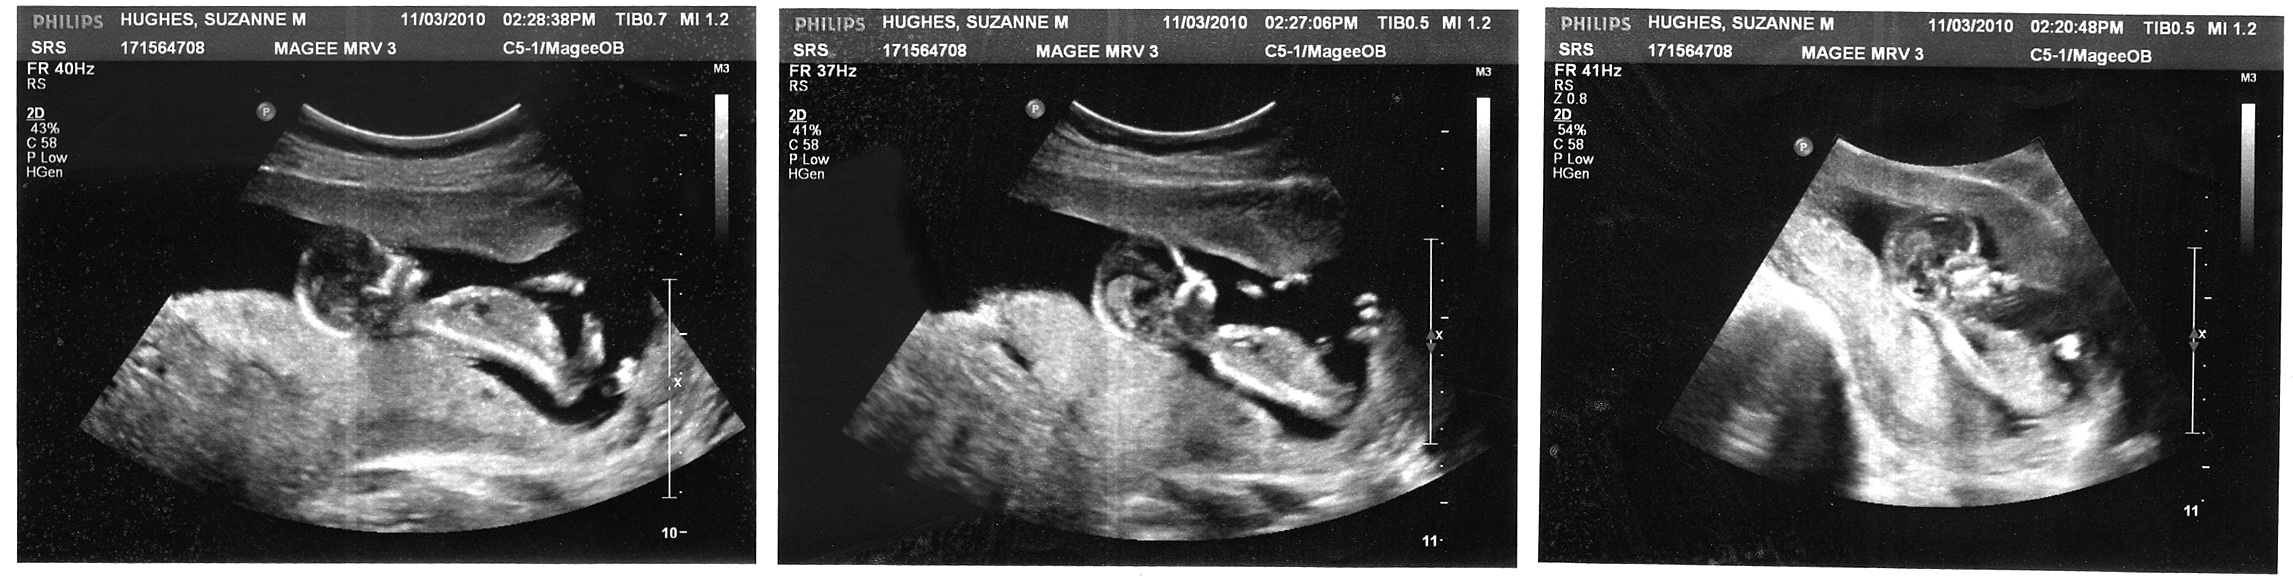

imageIn my last post (When Not In Control), I had mentioned that our daughter Reagan had died at 6 months. After uploading that post, I went back through my journal at the time of her death. I wanted to see where I was spiritually, mentally, not to mention emotionally. I discovered the journal entry and sonogram picture of Reagan that I want to share. Promises, especially from The Lord, are as real as my daughter Reagan.

When Sue’s sonograms were done, especially with her high risk pregnancy, one of the main things that doctors examined and intently watched is the heart and how it is distributing her blood. Are the arteries open and allowing the blood to flow properly? Are there any obstructions? Is the umbilical cord carrying the blood properly? And is the flow of the blood, from and to the heart correct? That is the one thing that is of central importance. However, more of that later.